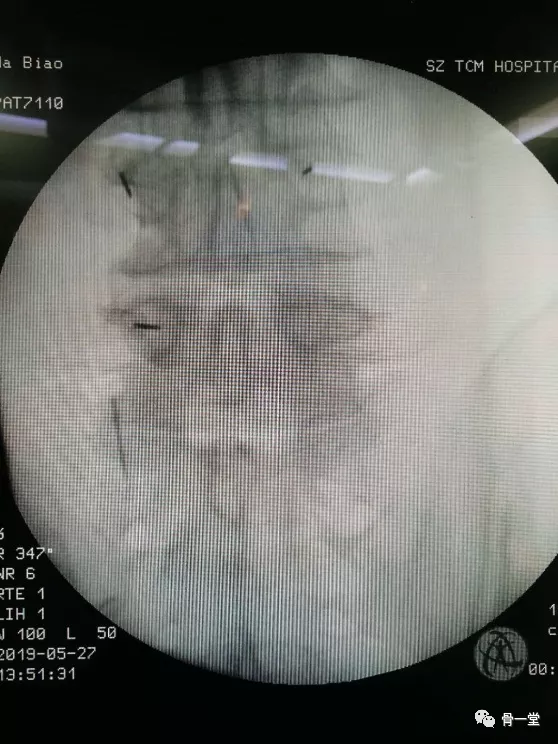

骨一科脊柱運動醫學學組團隊在蔣順琬教授的指導下經過術前充分準備,與患者詳細溝通後,微創手術如期進行。在麻醉科的密切配合下,術中採取小切口,打通工作通道,顯露突出的椎間盤,髓核摘除減壓後,準確植入融合器及釘棒系統,C型臂透視見各內固定器位置良好後,沖洗縫合切口,術中出血100ml,手術2.5小時,手術順利完成。術後第一天,患者下肢麻木厚重感就完全消失,感覺輕鬆,對前來查房的蔣順琬教授、馬篤軍主治醫師等連連感謝,術後第二天下地行走。現患者已治癒出院。

手術操作過程醫師站位